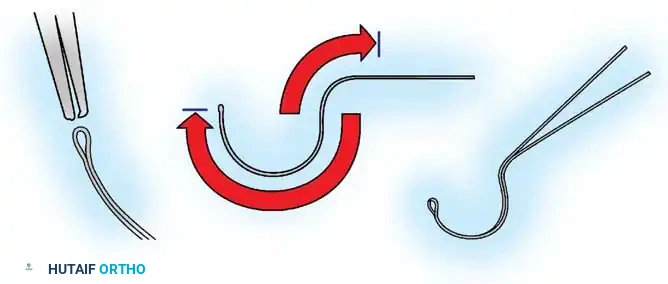

The Hall Technique

The Hall technique offers an alternative method for facet obliteration and grafting, particularly useful in rigid deformities.

Fig. 38-28: The Hall technique of facet fusion, involving sharp excision of the inferior facet and trough creation.

- Sharply amputate the inferior articular facet with a gouge and remove the bone fragment entirely. This exposes the cartilage of the superior facet.

- Remove the exposed cartilage completely with a sharp curet.

- Create a bleeding trough by removing the outer cortex of the superior facet.

- Impact cancellous bone grafts directly into this vascularized trough.

- Complete the procedure with global decortication of the posterior elements.